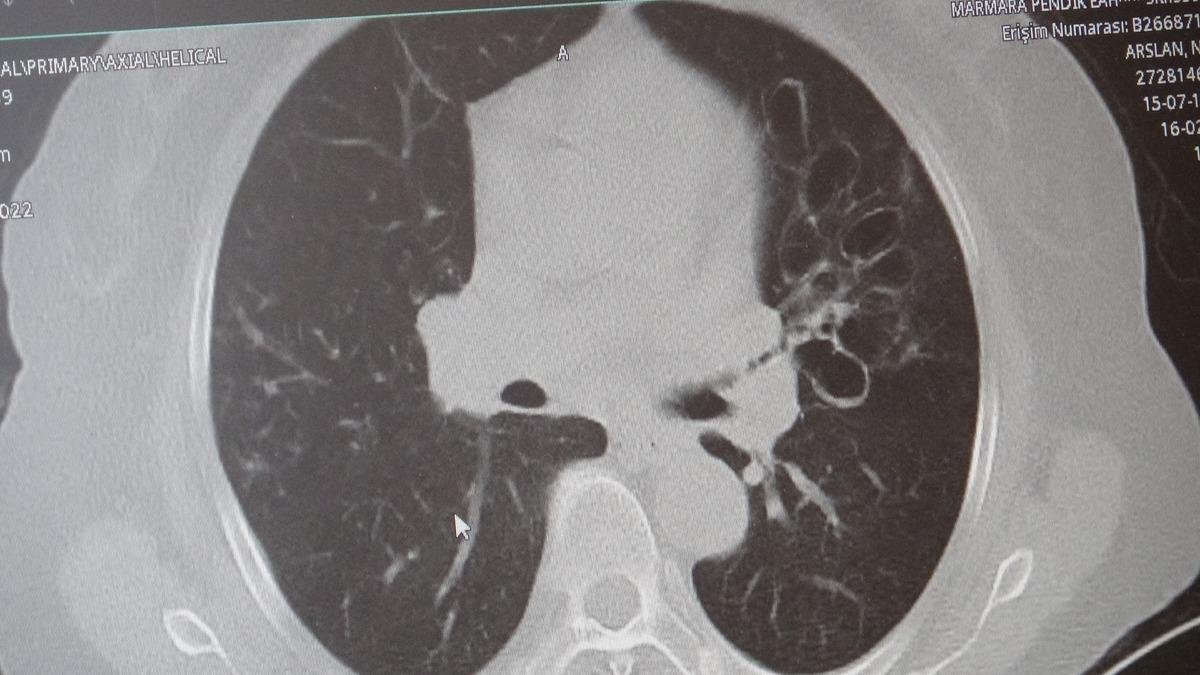

Marmara Üniversitesi Pendik Eğitim ve Araştırma Hastanesi uzmanlarından Prof. Dr. Sait Karakurt, dünya genelinde can kayıplarına neden olan hastalıklar arasında 4'üncü sırada yer alan KOAH ve beraberinde getirdiği zatürre riskine karşı önemli açıklamalarda bulundu.

KOAH, zararlı maddelerin akciğeri parçalamasıyla oluşan bir rahatsızlık ve bunun da en önemli nedeni sigara.

KOAH’ın akciğer dokusunu tahrip eden bir hastalık olduğunu ve bu nedenle de hastaların enfeksiyona açık hale geldiğine dikkat çeken Karakurt, "Akciğer dokusunun tahrip olduğu her durumda hastaların enfeksiyona karşı eğilimi artar ve enfeksiyona yakalandıkları zaman bunun geçmesi güç olur. KOAH'lı hastalar zatürre geçirdikleri zaman öksürük ve balgam artışı gibi bir takım belirtiler gelişir. Ayrıca ateşin 38,5 derecenin üstüne çıkması, nefes darlığının artması, titremeyle birlikte ateşin yükselmesi ve bir takım bilinç bozukluğu gibi belirtiler hastanın zatürre olduğunu gösterebilir. Bu nedenle hastaların erkenden doktora başvurmaları önemlidir" dedi.